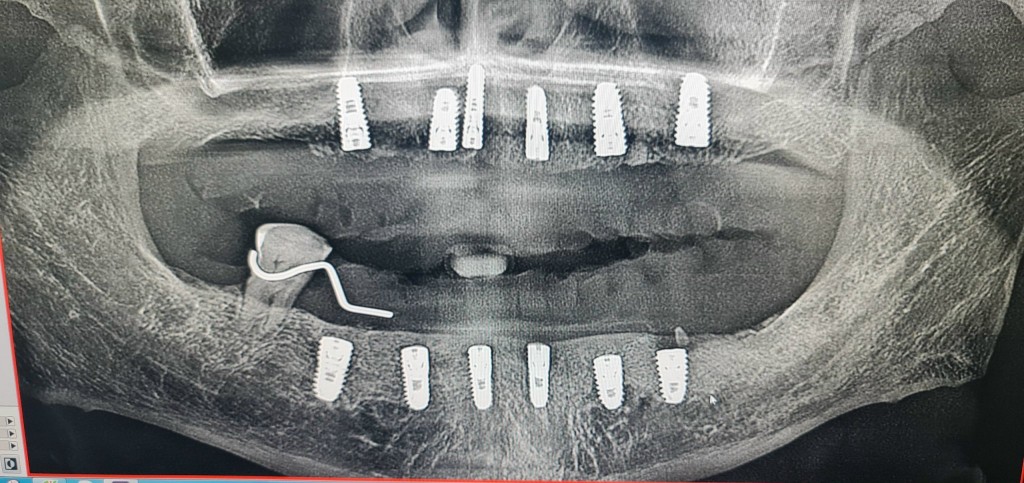

Theo đơn tố cáo, vào ngày 17/8/2022, ông T.T.D, người bệnh sinh năm 1954 và gia đình ông đã đưa ông T.T.D đến Nha khoa Miley Luxury để khám răng. Tại đây, ông T.T.D đã được tư vấn nhổ 20 chiếc răng và trồng mới 12 trụ Implant, nhằm phục hồi toàn bộ 24 răng sứ trong 2 hàm.

Theo thỏa thuận, gia đình ông T.T.D đồng ý trồng 12 trụ Implant của nhãn hiệu Alphadent, xuất xứ từ Đức, với tổng giá trị là 216 triệu đồng. Trước khi thực hiện quy trình lắp ghép răng, gia đình ông đã thanh toán trước 132 triệu đồng. Số tiền còn lại sẽ được thanh toán sau khi quy trình hoàn tất.

Ngày 23/5/2023, ông T.T.D quay trở lại Nha khoa Miley Luxury để tái khám và đặt Abutment, một khớp nối dùng để gắn kết trụ Implant trong xương hàm và răng sứ. Tuy nhiên, sau khi ông T.T.D thực hiện quy trình này và về nhà, ông bị đau nhức và được gia đình đưa đi khám tại Bệnh viện Răng Hàm Mặt TP Hồ Chí Minh. Kết quả chụp chiếu và xem lại hình ảnh CT 2 hàm, ông T.T.D nghi ngờ rằng Nha khoa Miley Luxury đã sử dụng trụ Implant không phải của nhãn hiệu Alphadent (Đức) như đã thỏa thuận.

Người nhà của ông T.T.D nghi ngờ rằng 12 trụ Implant mà Nha khoa Miley Luxury đã trồng không phải là của nhãn hiệu Alphadent (Đức). Thêm vào đó, ông T.T.D đã phát hiện thông qua phương tiện truyền thông rằng Nha khoa Miley Luxury đang bị Sở Y tế xử phạt và tước quyền sử dụng giấy phép hoạt động khám bệnh, chữa bệnh trong thời hạn 4 tháng kể từ ngày 2/6/2023.